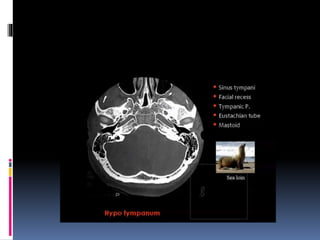

Imaging of the ear

Superior surface of petrous bone

Medial surface of petrous

bone